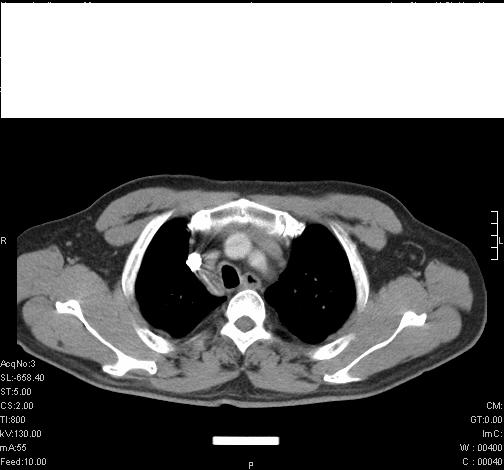

标题: CT6685:右肺阻塞性炎症,增强CT。 [打印本页]

标题: CT6685:右肺阻塞性炎症,增强CT。

前几天,发了患者的平扫片,患者抗炎一周后增强扫描。右中叶病灶吸收明显,但下叶病灶未见明显吸收。右肺门可见结节影,看来凶多吉少

第18幅,好像不能简单用炎症解释,前几天我发平扫时,90%人支持肺癌,现在好像大家更倾向于炎症了,我觉得还是不能排除肺癌。

还是考虑右肺中央型肺癌可能性大

考虑右肺中央型肺癌可能性大